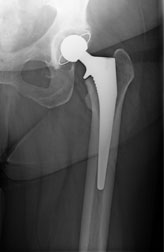

Nach Ausschöpfung aller konservativen Maßnahmen ist die operative Therapie bei einer röntgenologisch nachgewiesenen Coxarthrose mit erheblicher funktioneller Beeinträchtigung, sowie Beschwerden im Alltag und Beruf indiziert. Dabei werden normalerweise sowohl der Hüftkopf, als auch die Hüftpfanne ersetzt, man spricht daher von einer Totalendoprothese (TEP). Die Prothese kann dabei im Knochen durch Knochenzement verankert oder durch eine spezielle Oberflächenbeschichtung zementfrei fixiert sein. Von einer Hybrid-Implantationstechnik spricht man, wenn der Schaft einzementiert und die Pfanne zementfrei eingebaut wird.

Prothesen Hüfte: Prothese zementfrei / Prothese zementiert

Zementfreie Prothese mit Pressfit Pfanne